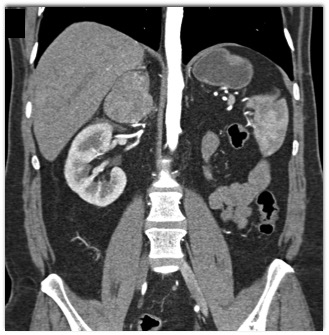

The most likely diagnosis of the right adrenal mass is?

hematoma

pheochromocytoma

metastatic renal cell carcinoma

primary adrenal cortical carcinoma